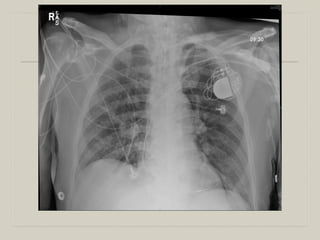

  32 WF with ESRD on HD through a Permcath admitted with AMS.

  Temp 102.3. BP 82/32. HR 130, RR 30

  CBC 11.4, 9/36, 55

  ABG 7.2, 9, 34 on 28% O2